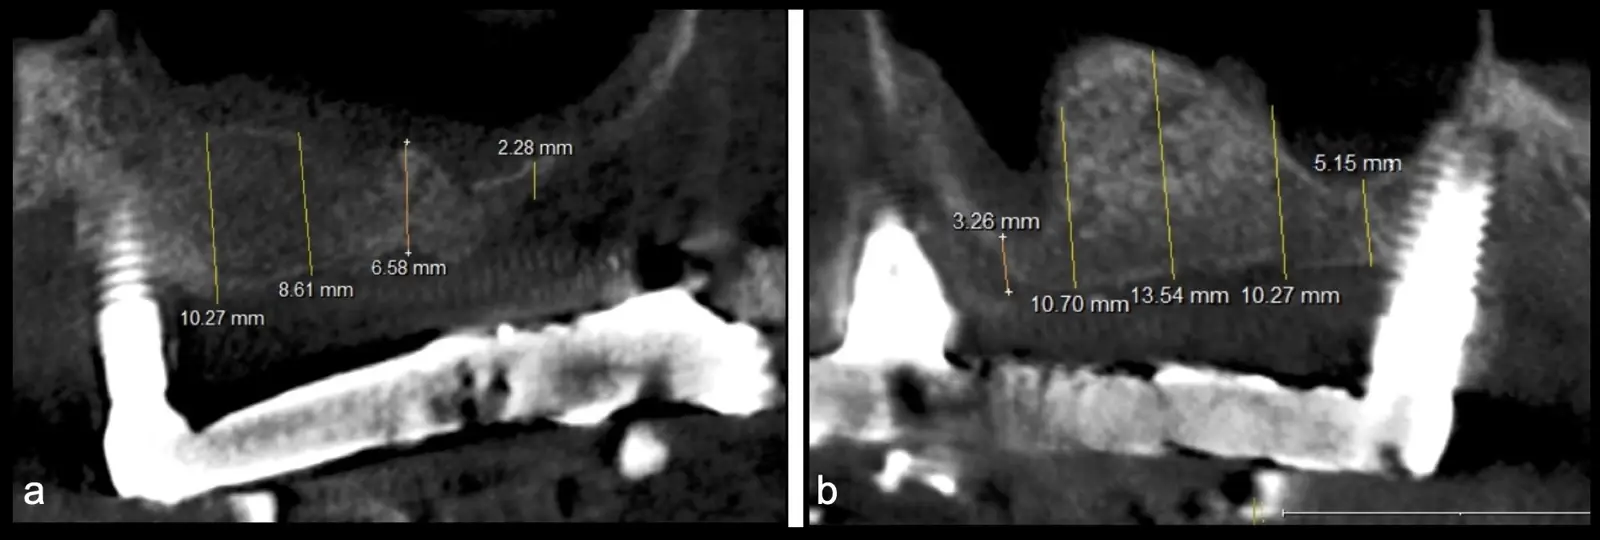

Figura 2. Espesor de la pared lateral (X), altura del reborde residual (Y), profundidad del seno maxilar (Z) y espesor de la membrana sinusal.

El tipo de inserto a ser utilizado dependerá del espesor de la pared ósea. Si la pared es menor a 0.5 mm, es mejor utilizar insertos de desgaste para prevenir la ruptura de la membrana de Schneider; si el espesor es mayor a 0.5 mm, se puede utilizar insertos de corte de espesor medio (Figura 3).